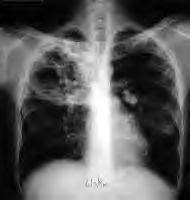

Worst areas included drug misuse, new cases in Tuberculosis, diabetes and male life expectancy which sits at 76.

WHAT'S NEW IN TUBERCULOSIS